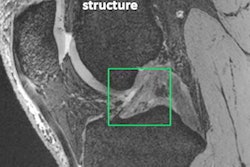

The 7-tesla PET/MRI scanner. Image courtesy of MR Solutions.The system enables PET and MRI images together or separately for both soft-tissue contrast and molecular imaging, and it features a large axial 15-cm field-of-view with the PET module and a 24 cm bore with MRI alone, according to the vendor.